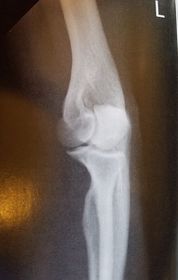

| AP Elbow | humerus is externally rotated because the epicondyles are not in profile |

| AP Elbow | ANATOMY: distal humerus - proximal forearm CRITERIA: slight superimposition of proximal radius/ulna humeral epicondyles in profile open joint space POSITIONING: CR perpendicular @ midelbow |